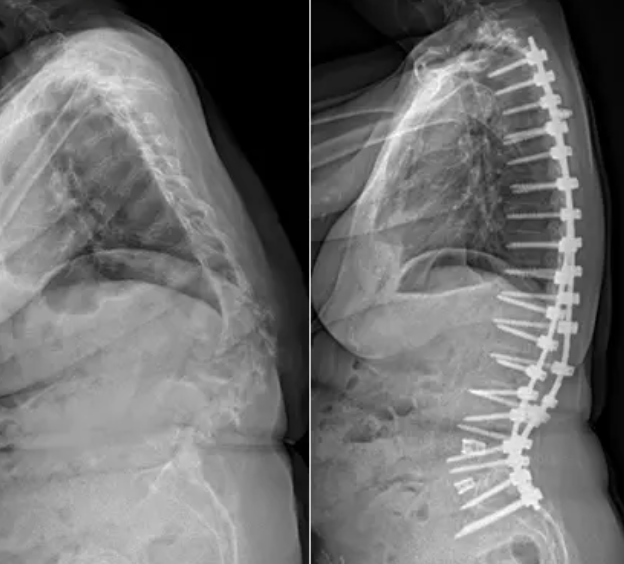

Complex Spine Problems and Deformity Correction

Specialized care focused on improving quality of life and restoring your ability to return to daily activities

Gallery

Explore our advanced spine care techniques.